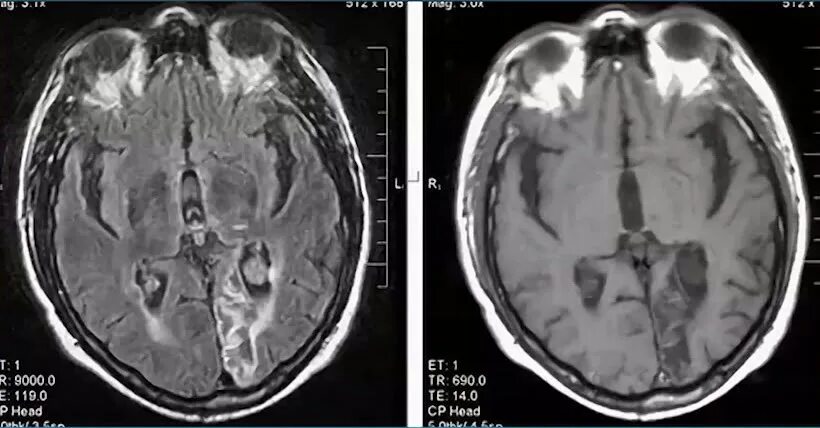

Глиозные изменения головного мозга на мрт